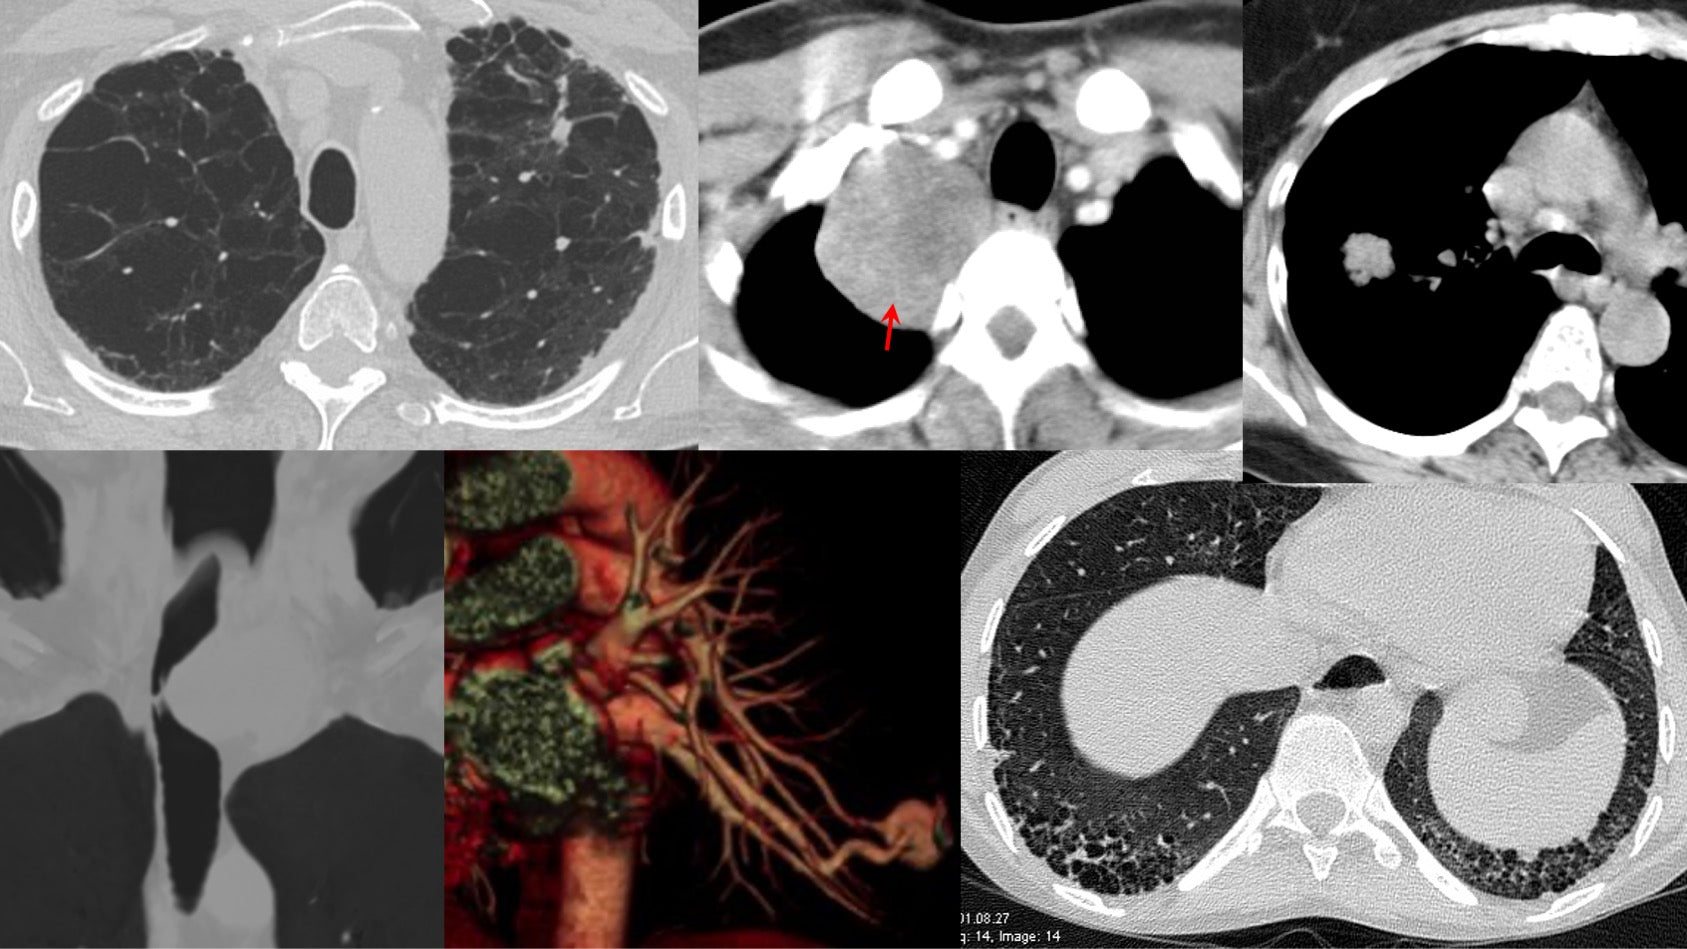

Computed Tomography of Interstitial Lung Diseases

Known Unknowns of Everyday Radiology Practice a Practical Radiology Handbook